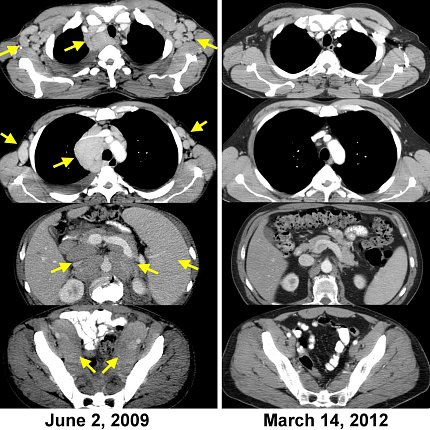

Black and white CAT scans show areas of cancer in June 2009 and, on the right, a clean scan with no tumors

CAT scans of the first patient to respond to treatment with adoptive transfer of autologous lymphocytes genetically engineered to express a chimeric antigen receptor (CAR) targeting CD19. The left side shows the lymphoma burden; at right, complete cancer regression ongoing more than 10 years later.

“We treated the first patient ever to receive these CAR-T cells in 2009. He underwent a complete regression and is disease-free more than 12 years later,” Rosenberg said.